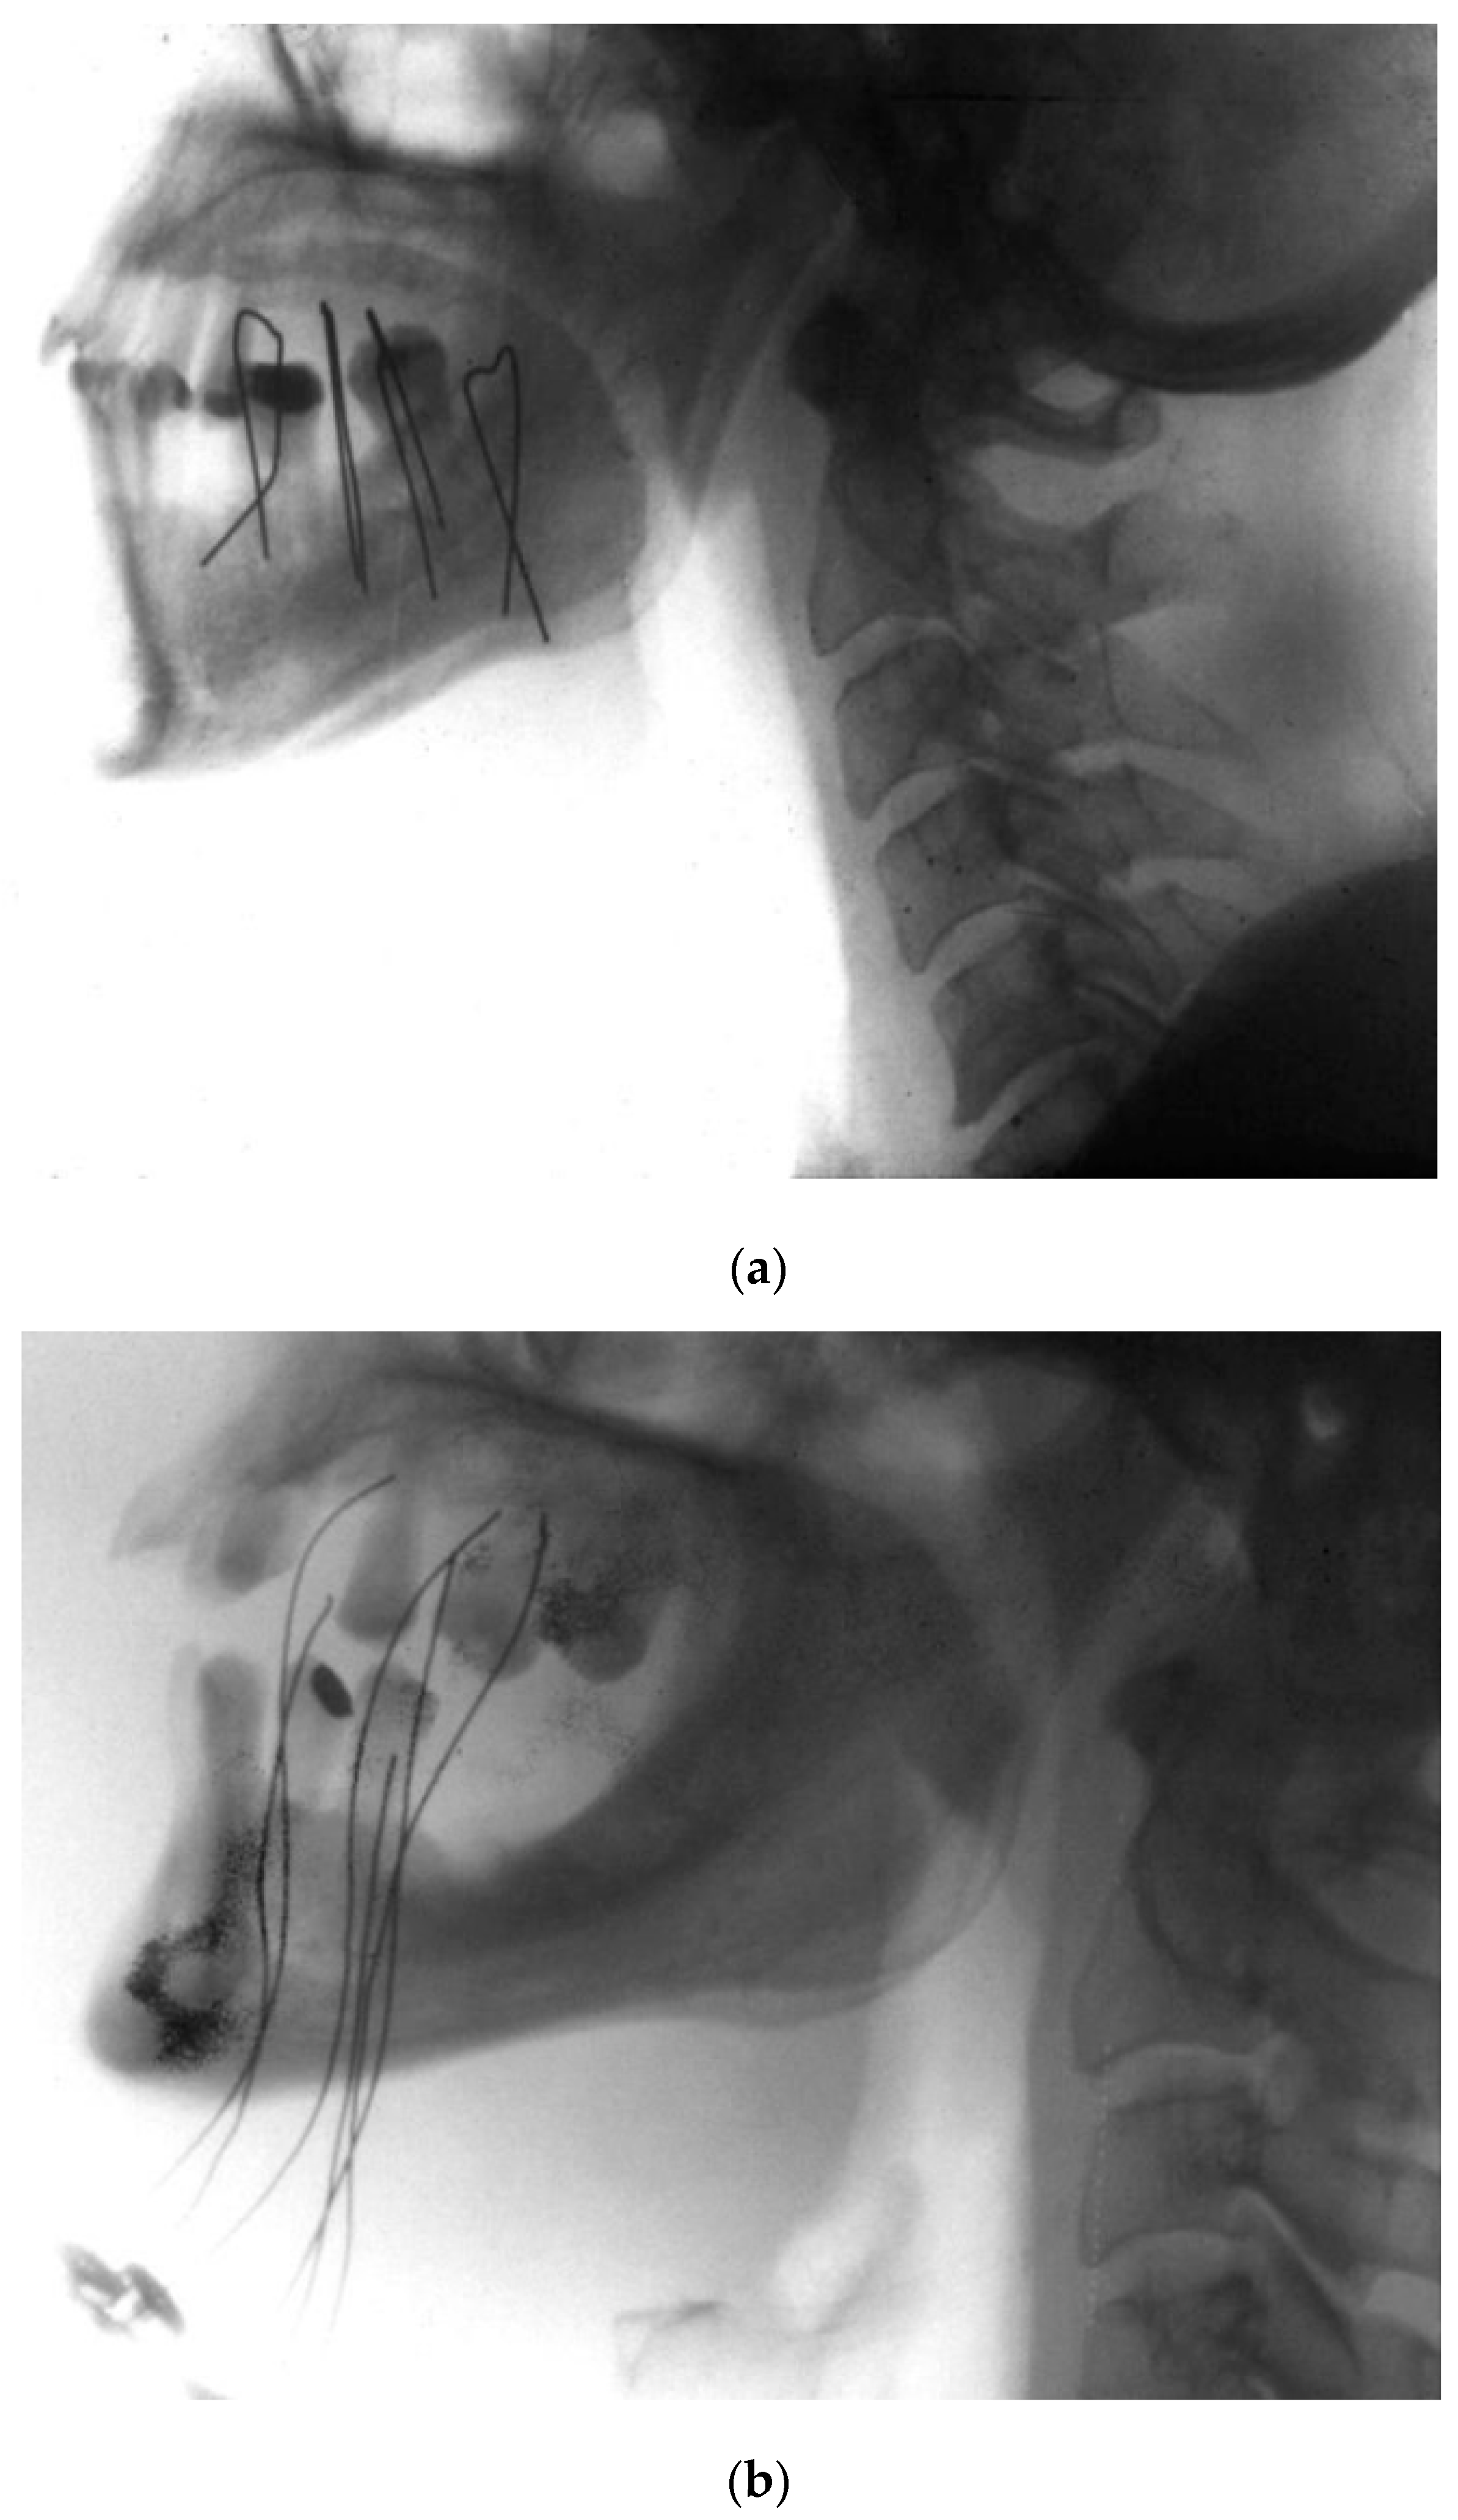

- Kovács, G.; Martinez-Monge, R.; Budrukkar, A.; Guinot, J.L.; Johansson, B.; Strnad, V.; Skowronek, J.; Rovirosa, A.; Siebert, F.A.; GEC-ESTRO Head & Neck Working Group. GEC-ESTRO ACROP recommendations for head & neck brachytherapy in squamous cell carcinomas: 1st update—Improvement by cross sectional imaging based treatment planning and stepping source technology. Radiother. Oncol. 2017, 122, 248–254. [Google Scholar] [CrossRef] [PubMed]

- García-Consuegra, A.; Gimeno Morales, M.; Cambeiro, M.; Tagliaferri, L.; Kovacs, G.; Van Limbergen, E.; Ramos, L.I.; Manuel Arnaiz, J.; Alcalde, J.; Lecanda, F.; et al. Dose volume histogram constraints in patients with head and neck cancer treated with surgery and adjuvant HDR brachytherapy: A proposal of the head and neck and skin GEC ESTRO Working group. Radiother. Oncol. 2021, 154, 128–134. [Google Scholar] [CrossRef] [PubMed]